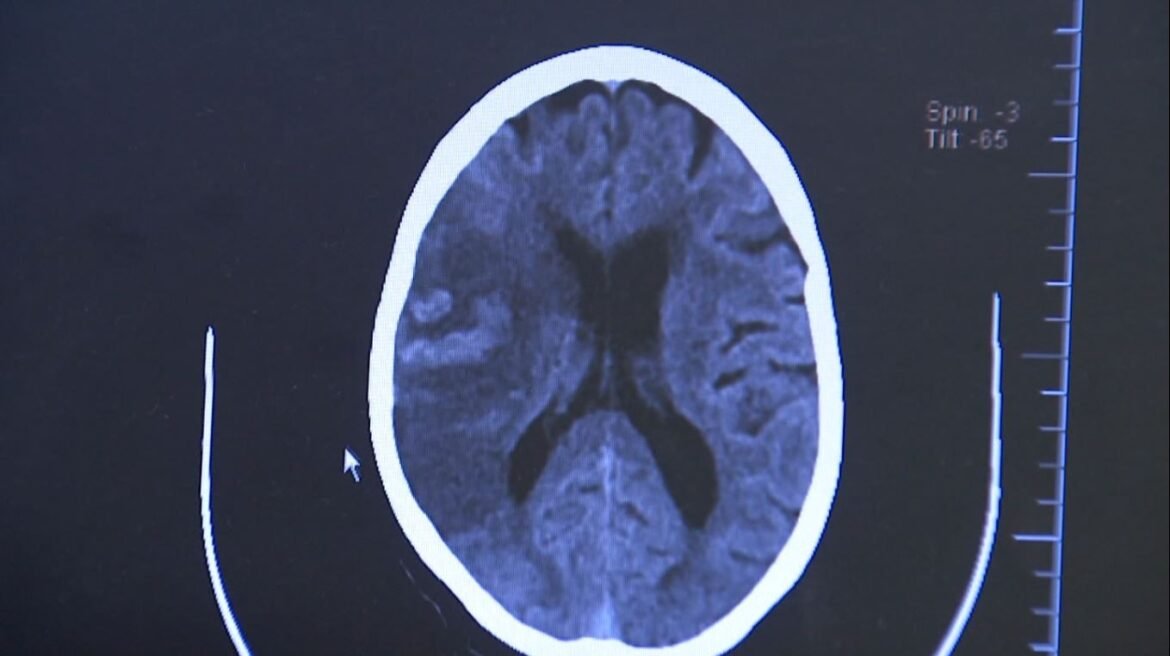

O diagnóstico é feito por tomografia computadorizada ou ressonância magnética do crânio. “Esses exames permitem detectar a área afetada e definir se é um AVC isquêmico ou hemorrágico”, diz Chaddad.

Durante o AVC isquêmico há um bloqueio na artéria, levando à falta de sangue e morte das células cerebrais. Já no hemorrágico, o sangue extravasa por ruptura de um vaso

“Durante o AVC isquêmico há um bloqueio na artéria, levando à falta de sangue e morte das células cerebrais. Já no hemorrágico, o sangue extravasa por ruptura de um vaso”, explica o neurocirurgião Feres Chaddad, professor da Universidade Federal de São Paulo (Unifesp) e chefe da neurocirurgia da BP – A Beneficência Portuguesa de São Paulo.